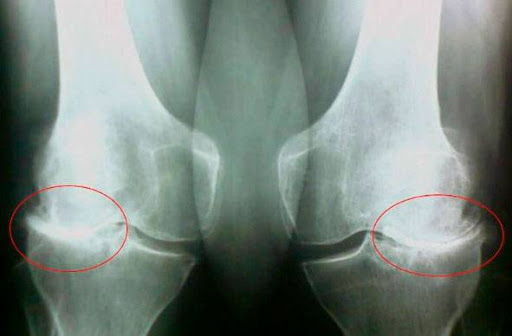

Заседналият начин на живот, стресът, излишъкът от сол и захар в храната — всичко това омекотява хрущялната тъкан, износва я и я изтънява. С всяко ново движение хрущялът се износва и деформира, костите започват да се трият една в друга, причинявайки непоносима болка.

Ревматоидният артрит и остеоартритът могат да доведат до инвалидност след 3-5 години от началото на заболяването и могат да съкратят продължителността на живота на пациентите с 15-20 години!

Не се шегувайте с артроза и артрита! Заболяванията на ставите ще ви доведат до инвалидна количка за по-малко от 3 години!